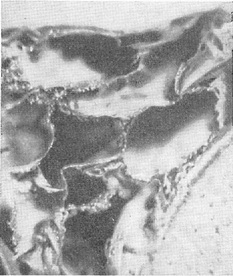

Ликвороносные канали - це мережа трубок, діаметр яких коливається від 3 мм до 200 мк (рис. 5). Найбільші канали повідомляються з цистернами основи мозку. Звідси канали поширюються по борознах великих півкуль і переходять на звивини. На своєму шляху канали рясно галузяться та анастомозують між собою. В ендотеліальних стінках каналів є отвори, за допомогою яких вони з'єднуються з ячеями. Канали - головні річища руху спинномозкової рідини. Цей рух має турбулентний характер і є вираженням двох по суті різних типів руху рідини: направленого від місця утворення до місця відтоку і коливального руху, обумовленого пульсацією судин, диханням і скороченням мускулатури.

![]() Рис. 5. Ликвороносный канал з розташованої в його просвіті артерією - поперечний переріз (микростереофотография трахископического препарату).  |